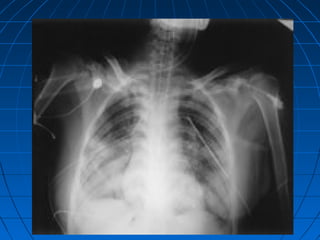

Chest X-ray

of a victim

of

bombing

attack

showing

typical

bilateral

patchy

infiltrates in

a butterfly

distribution.

 • Chest radiography is necessary for

anyone who is exposed to a blast.

 A characteristic “butterfly” pattern may be

revealed upon x-ray.

““Blast Lung”Blast Lung”

White Butterfly SignWhite Butterfly Sign

Chest X-ray of avictim of bombing attack showing typical bilateral patchy infiltrates in a butterfly distribution.

BLI’s ManagementBLI’s Management Diagnostic Evaluation  • Chest radiography is necessary for anyone who is exposed to a blast.  A characteristic “butterfly” pattern may be revealed upon x-ray.  • Arterial blood gases, computerized tomography, and doppler  technology may be used.  • Most laboratory and diagnostic testing can be conducted

““Blast Lung”Blast Lung” WhiteButterfly SignWhite Butterfly Sign